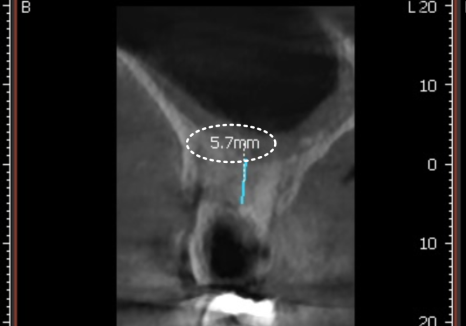

그래서 저희는 수술 전 정밀 CT를 통해

신경관과 상악동의 위치를 아주 꼼꼼하게 파악하고,

수술 중간중간에도 정확한 식립을 위해

CT 촬영을 병행합니다.

0.1mm의 오차도 허용하지 않고,

계획한 위치에 임플란트가 안전하게 들어갔는지

실시간으로 확인하기 위해서입니다.